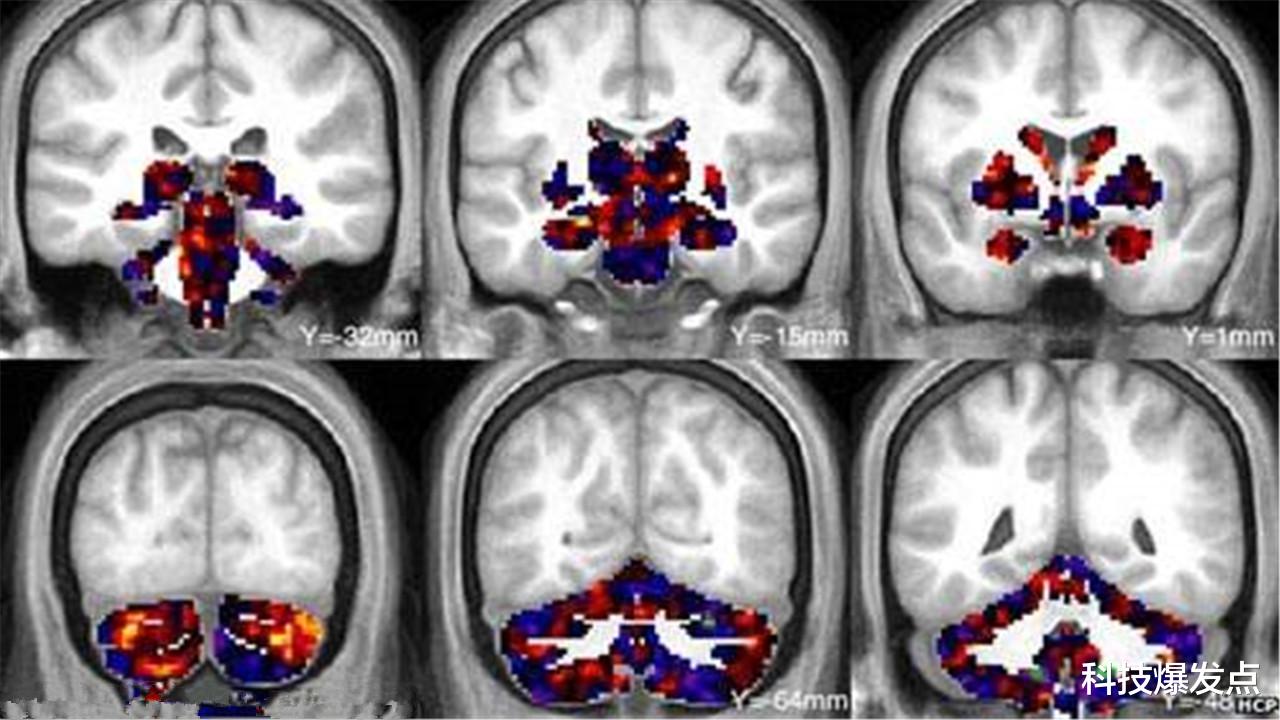

不难发现 , 国际空间站中的宇航员 , 他们并不是长期驻守 , 而是美国100多天就会返回地球一次 , 针对于11名宇航员 , 科学家进行了不同的研究 。 在他们返回地球之后 , 首先对大脑进行了磁共振成像 , 发现在来回往返于地球和太空中的宇航员 , 他们的大脑出现了微妙变化 。

在微重力的环境下 , 大脑当中的白质和灰质部分变化最为明显 , 脑脊液增多 , 脑室扩大 , 这都是在失重情况下所导致的 , 通过这样的改变 , 让大脑以及神经系统来适应微重力的环境 。 曾经有一对双胞胎宇航员 , 他们的身体中拥有着同样的DNA遗传物质 , 当兄弟中一人进入太空生活100多天后返回地球 , 发现他们身体中的DNA都发生了变化 , 虽然有着一样的长相 , 但是遗传物质却发生了改变 , 整个过程是不可逆的 。 如果只是大脑的神经系统为了适应重力环境而对灰质和白质作出的调节 , 再回到地球 , 适应了重力环境之后 , 神经系统也会再次恢复 。